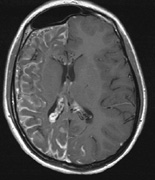

Mental retardation and seizures in TSC are often associated with benign CNS astrocytic hamartomas.131 On imaging, the cerebral lesions show three patterns:132

1. Superficial cortical sclerosis (parenchymal hamartoma) which distort the gyri. Microscopy shows large atypical fibrillary type astrocytes with few associated neurons and areas of calcification.133 The numerous abnormal glial processes and fibers make the tissue abnormally firm or “sclerotic” on palpation (Fig. 13).132

2. Subependymal nodules (SEN) are typically found along the lateral borders of the ventricles and parehncymal brain lesion (“cortical tubers”) (Figs. 14 and 15). Calcification in the first year of life is rare.132

On MRI imaging, the subependymal nodules and parenchymal brain lesions of infants (age ≤3 months) and adults show different signal characteristics. Infant CNS tubers are hyperintense on T1-weighted images and hypointense on T2-weighted images, which is the opposite of the pattern seen in adults.134 Malignant transformation of SEN occurs in about 10% to 15% of patients and the resultant subependymal giant cell astrocytoma accounts for 25% of premature deaths in TSC.135,136

Fig. 15. Tuberous Sclerosis Complex. (a) Patient 1: Axial CT scans demonstrating typical calcification of subependymal nodules in a 13-year-old girl with a history of seizures. (b and c) Patient 2. (b) Axial T2-weighted images demonstrate calcified subependymal nodules (arrowheads) and cortical tubers typical of tuberous sclerosis. (c) Widespread cortical tubers are seen on a coronal FLAIR sequence as thickening of the cortex and high signal of the subcortical white matter.